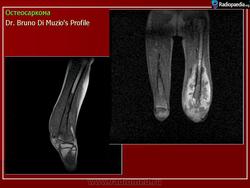

Рентгенологическая картина. Типичной картиной является наличие очага смешанной деструкции кости с разрушением кортикальной пластинки и формированием мягкотканного компонента опухоли. В процессе роста опухоли, периост приподнимается или отслаивается от коркового слоя, это вызывает новое костеобразование, обычно проксимальнее основного узла, данное явление получило название козырька Кодмана. Зона поражения на рентгеновском снимке имеет различную плотность, а характер матрикса часто облаковидный. КТ и МРТ могут играть важную роль в определении распространенности опухолевого процесса. Радионуклидное сканирование скелета выявляет «skip» метастазы, многоузловые опухоли, системное поражение. В ряде клиник принято использовать артериографию, так как остеосаркомы - гиперваскуляризованные опухоли.

Диагностика. Ведущим диагностическим методом, наряду с клиникой, является рентгенография. Характерно наличие очага деструкции кости, не имеющего четких контуров. Отсутствует зона склероза вокруг очага деструкции. Кортикальный слой кости разрушен. Сравнительно рано выявляется выход опухоли в окружающие мягкие ткани. Выделяются центральная и периферическая формы, а по характеру очага деструкции: остеолитическая — бесструктурный очаг разрушения кости, остеопластическая форма — очаг деструкции с участками склероза и уплотнения, смешанная форма — сочетание участков остеодитической и остеопластической форм. Во всех случаях очаг деструкции не имеет четких контуров. Характерна периостальная реакция в виде козырька Кодмэна или спикулообразного (игольчатого) периостита. В экстраоссальном компоненте опухоли возможны участки оссификации (патологическое костеобразование). На ранних стадиях заболевания опухоль может проявляться центрально или эксцентрически расположенным литическим очагом деструкции небольших размеров, с нечеткостью контуров кортикального слоя на ограниченном протяжении. Деструкция быстро нарастает и уже через 2-3 недели определяются вышеописанные типичные рентгенологические симптомы. Патологические переломы чаще наблюдаются при литических формах.. Характерно гематогенное метастазирование в легкие.